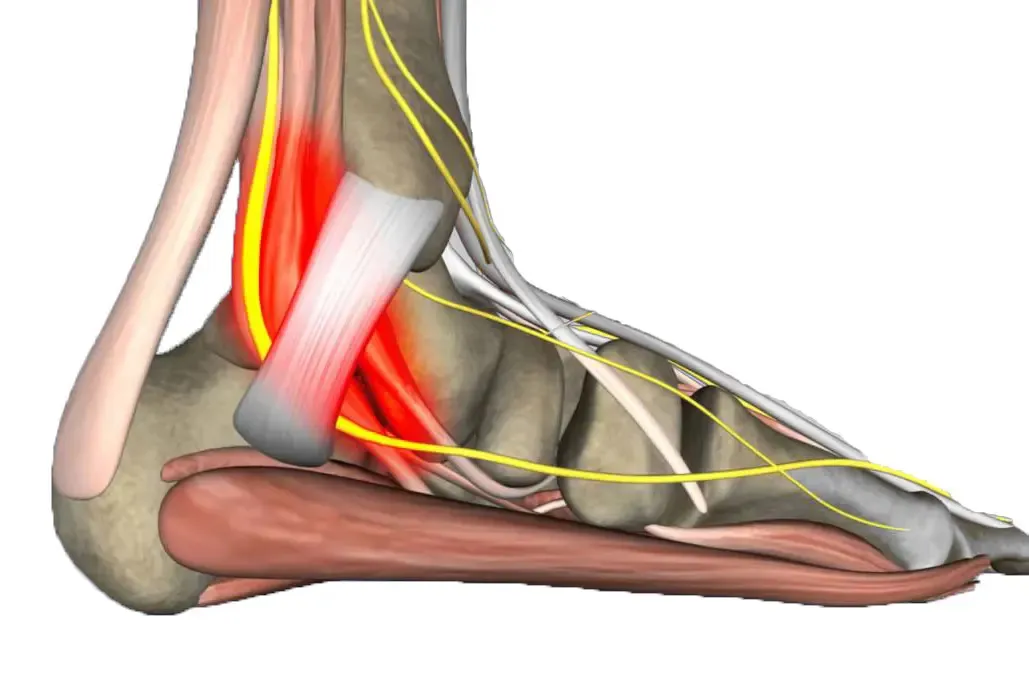

Fascitis Plantar: La Verdadera Culpable de tu Dolor

¿Qué es la Fascitis Plantar?

La fascitis plantar, o más correctamente fasciosis plantar, es la inflamación y degeneración de la banda de tejido conectivo que va desde el talón hasta los dedos del pie. Esta es la verdadera causa del 90% de casos de dolor de talón.

Tecnología Diagnóstica de Vanguardia en CPH

- Visualización directa de la fascia plantar engrosada

- Medición precisa del grosor fascial (normal <4mm)

- Detección de roturas parciales o completas

- Evaluación vascular con Doppler color

- Diagnóstico diferencial con otras patologías